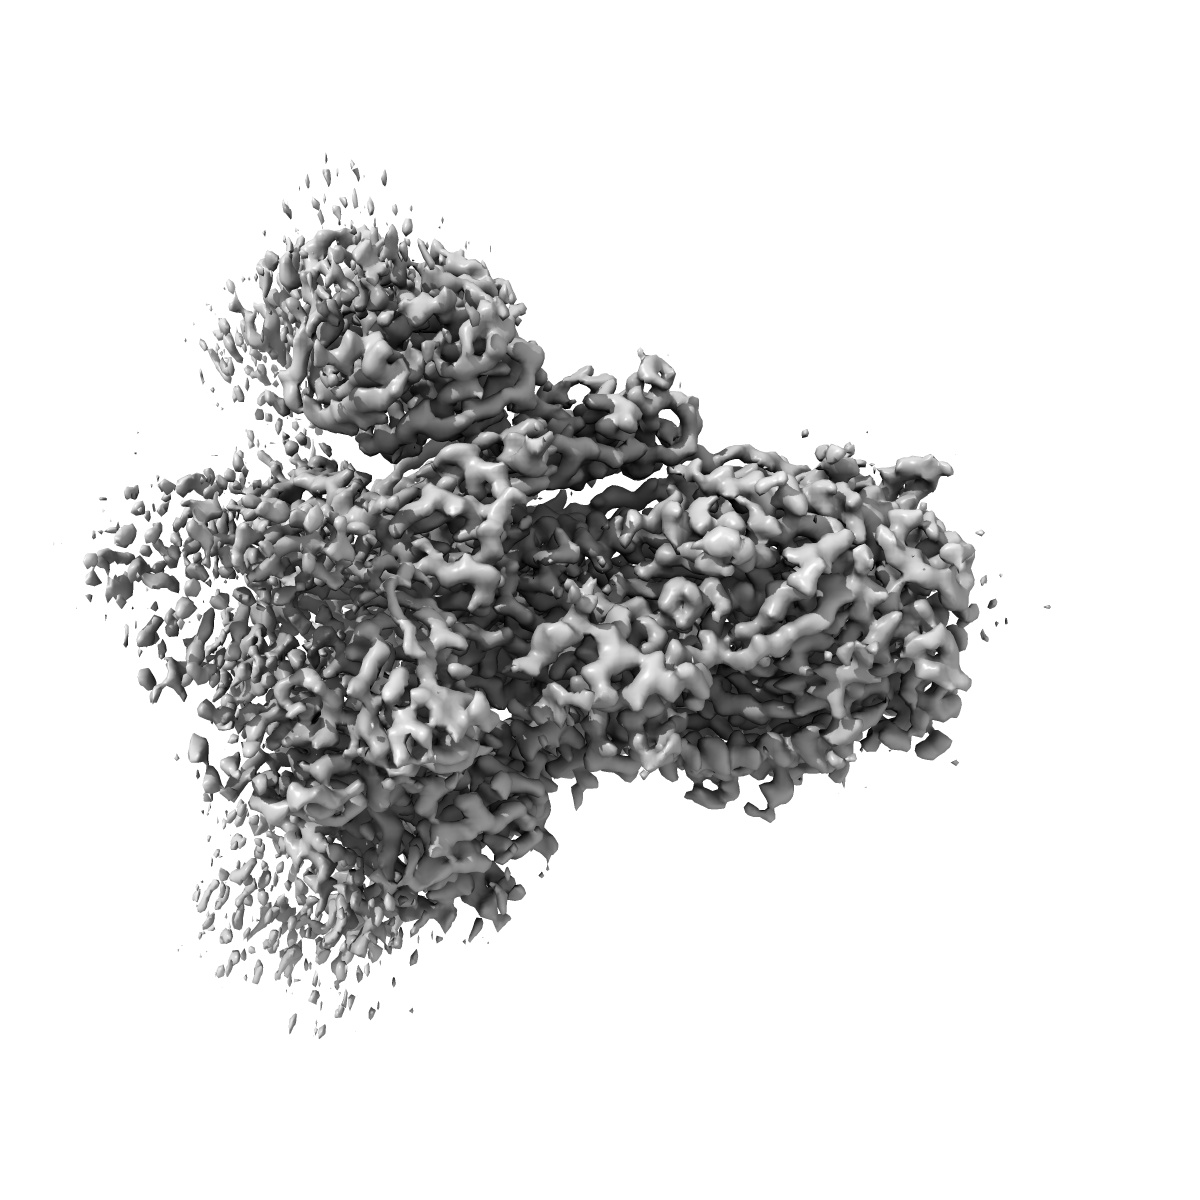

EMD-34042

SARS-CoV-2 BA.2.75 S Trimer in complex with XG2v024

Single-particle3.62 Å

Sample: BA.2.75 S trimer in complex with XG2v024

Characterization of the enhanced infectivity and antibody evasion of Omicron BA.2.75.